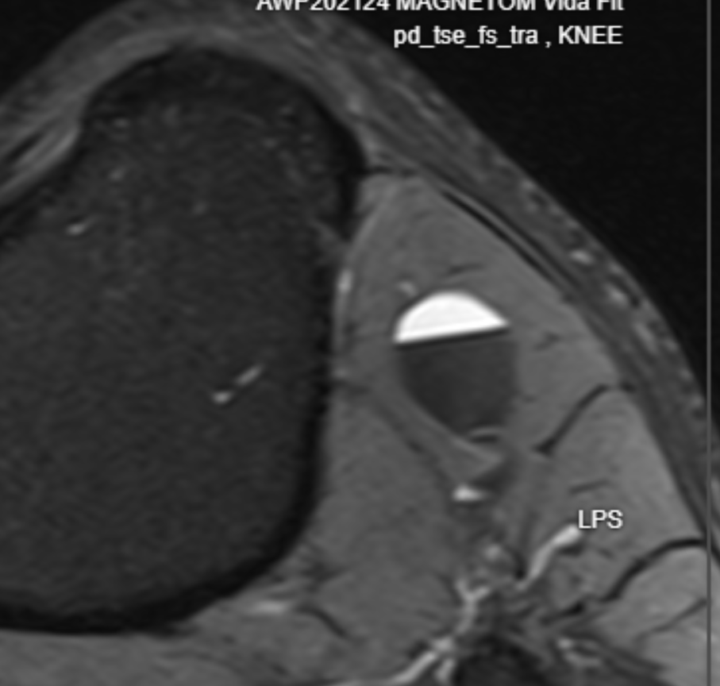

Knee MR arthrography.

Male 26 yo. Car crash 7 y ago. Prior simple MRI - partial ACL tear (hight grade). No medial meniscus pathology. I see this fragment inferior to medial meniscus, but not sure if its fragment or smth else. Any insights? Case at cmrad --> https://www.cmrad.com/cases/1779861922